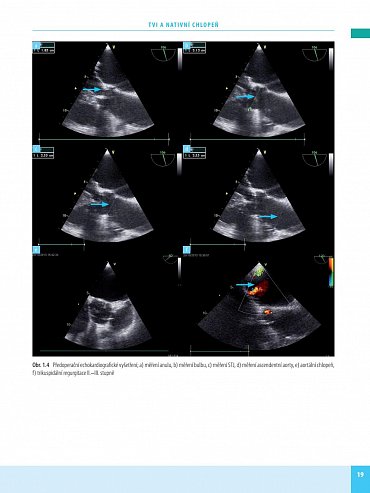

Transkatétrová implantace chlopní (TVI) je minimálně invazivní výkon umožňující náhradu poškozené srdeční chlopně - aortální nebo mitrální. Preferuje se zejména u pacientů s vysokým rizikem komplikací chirurgického výkonu na otevřeném srdci. Kniha obsahuje velký počet pečlivě vybraných kazuistik se stručným schématem diagnostického postupu, diferenciální diagnostikou a technikou operace. Vlastní popis je doplněn množstvím zobrazovacích vyšetření a peroperačních fotografií, které umožní orientaci čtenáře a pochopení základních kroků diagnostiky a léčby.